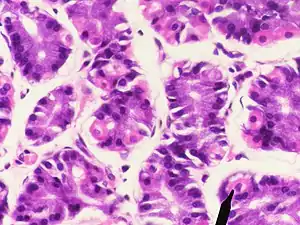

Парієтальні клітини

Парієтальні клітини (також парієтальні екзокриноцити) — епітеліальні клітини шлунка, що секретують хлоридну кислоту та внутрішній антианемічний фактор. Ці клітини розміщуються у власних залозах шлунка в товщі його дна та кардіального відділу. Відносно головних екзокриноцитів клітини розміщені поодиноко між ними в ділянці тіла і дна власних залоз шлунка.